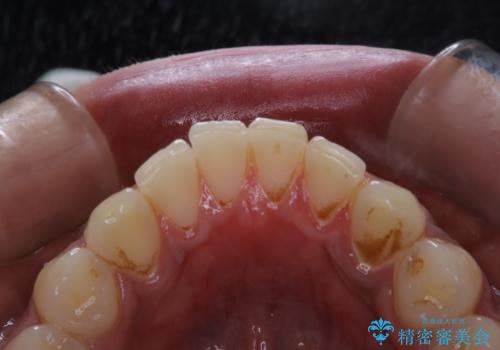

歯についたタバコのヤニをPMTCで綺麗に

- 電子タバコを吸う習慣があり、ステインがついてしまっている見た目が気になるとのことで来院されました。ステインだけではなく、歯石も全体的に付着していたためPMTC60分コースを行いました。